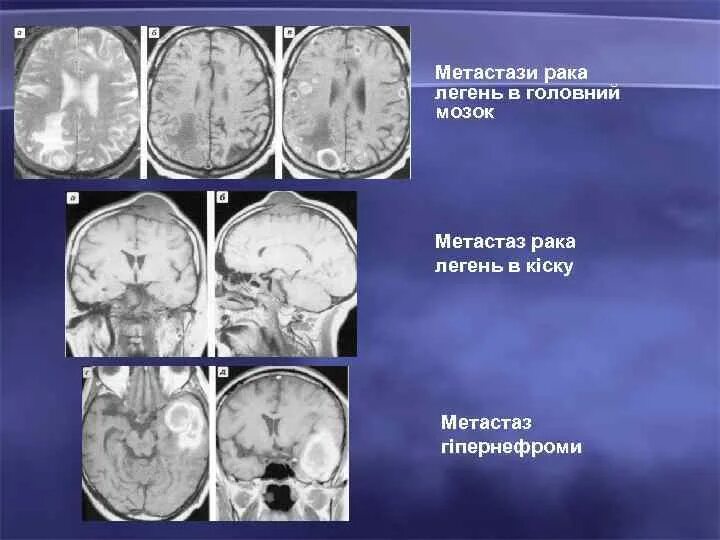

Отек мозга метастазы